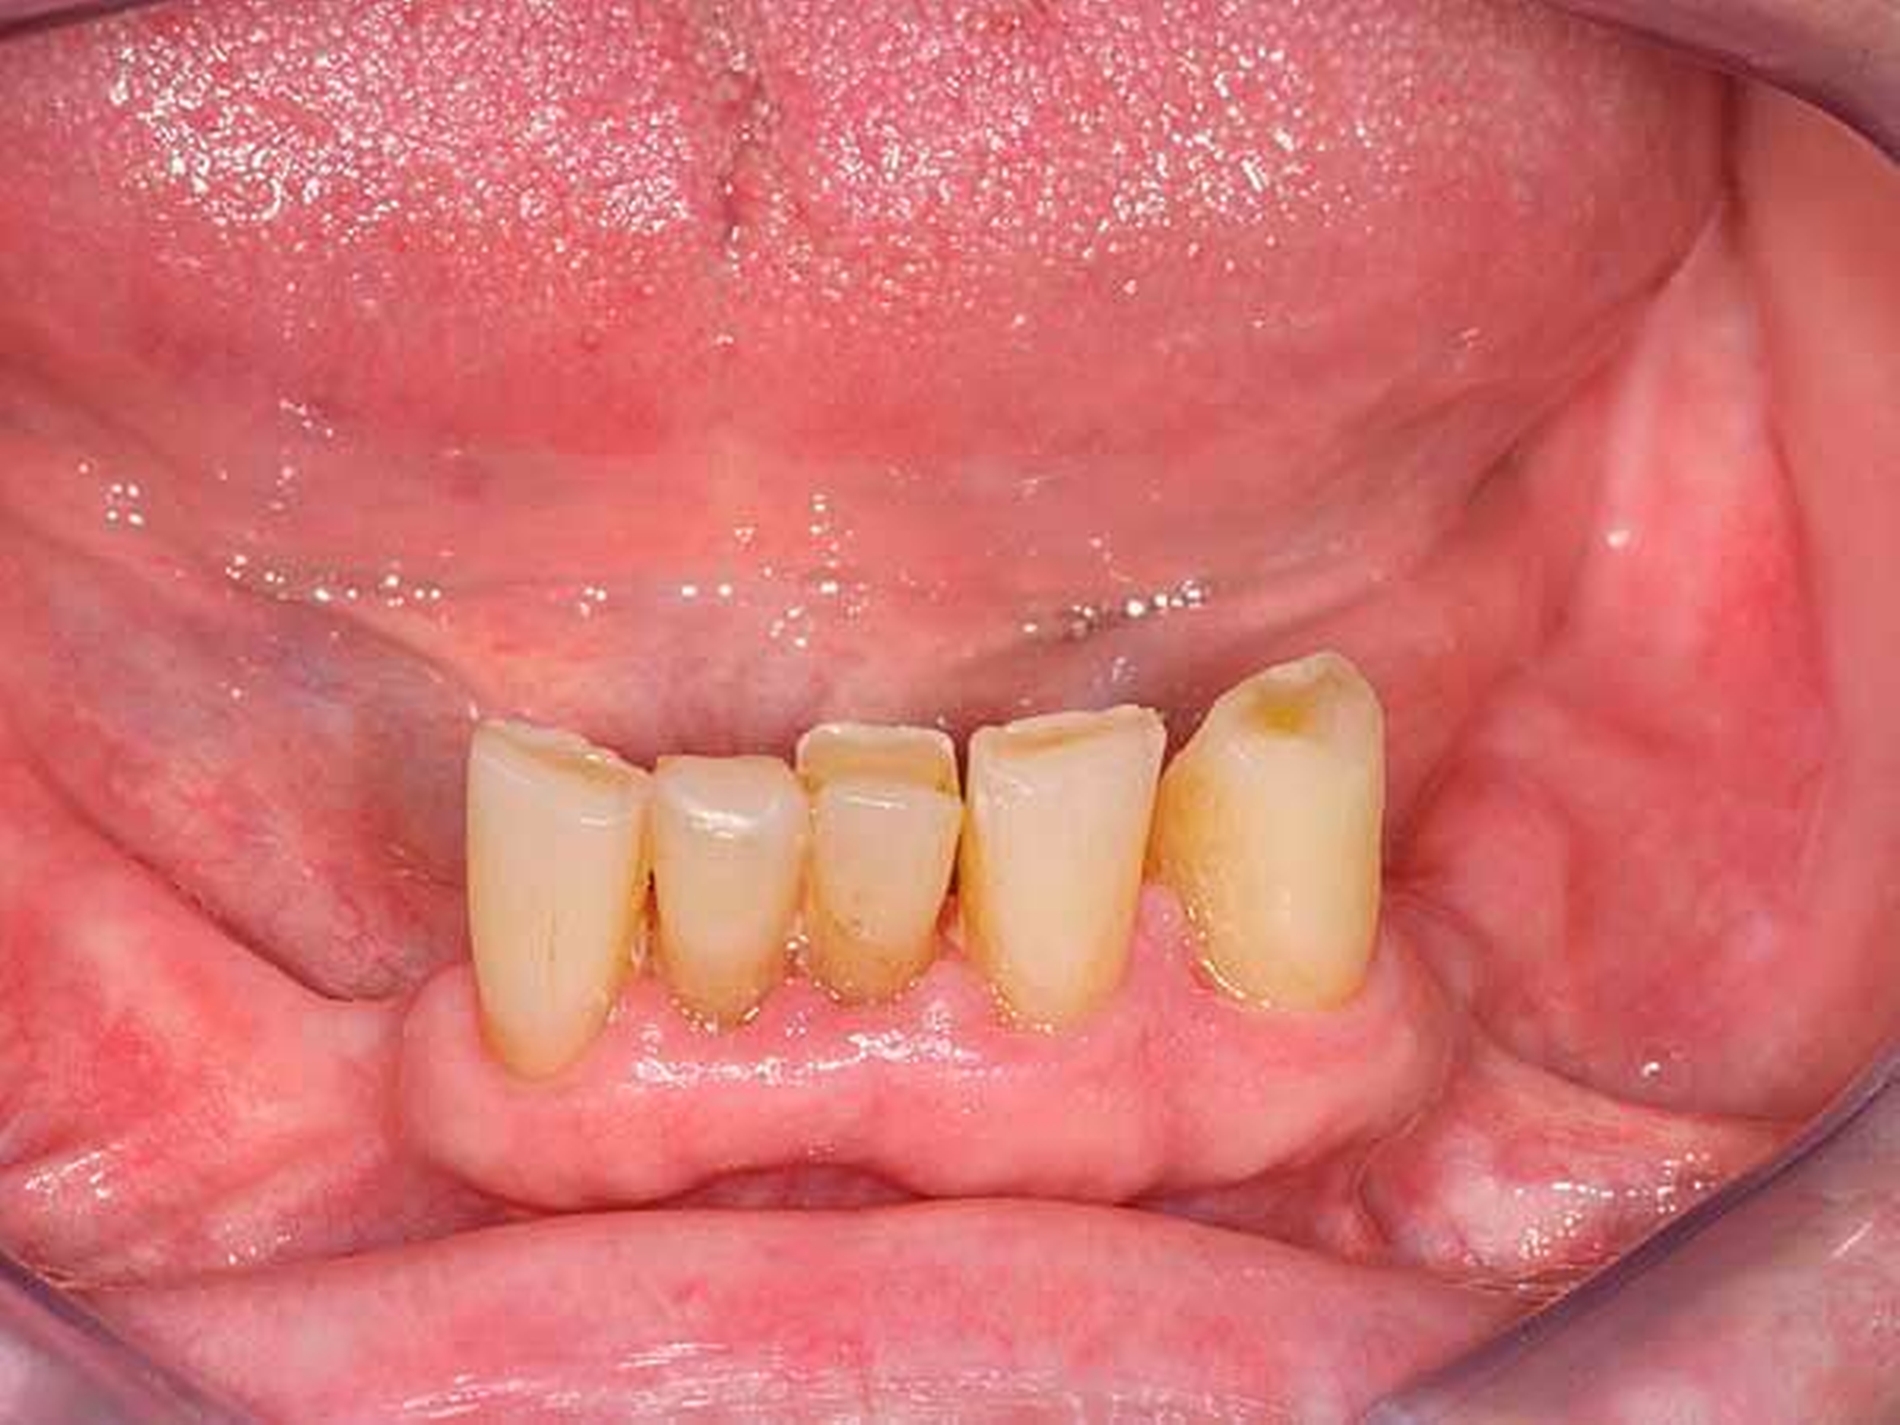

Im Oberkiefer gestattete die Lückengebisstopografie festsitzenden Zahnersatz gemäß den Richtlinien der gesetzlichen Krankenkassen. Im Unterkiefer verblieb nach Extraktion ein karies- und füllungsfreies anteriores Restgebiss von 34 nach 45 (Abbildung 2). Versorgungen mit implantatgestütztem Zahnersatz oder kombiniert festsitzend-herausnehmbarem Zahnersatz schieden aus Kostengründen aus. Angesichts der normalerweise sichtbaren Gussklammer-Verankerungen an den Prämolaren fürchtete die junge Frau eine Demaskierung als Prothesenträgerin.

Die Patientin konnte mit einer Modellgussprothese und zwei RPI-Klammern an den Zähnen 34 und 45 erfolgreich versorgt werden (Abbildungen 3 und 4). RPI steht für Rest (meist sattelferne Abstützung), Proximal Plate (approximale Führungsfläche), l-bar (i-förmiger Retentionsteil). Das RPI-Klammersystem wurde 1963 von Kratochvil [Kratochvil, 1963] eingeführt und von Krol 1973 [Krol, 1973] weiterentwickelt. Das Klammersystem ist kein Exot. Es findet sich in nahezu allen internationalen Standardlehrbüchern der Prothetik und gilt als das mit am besten bewährte Klammersystem für die bilaterale Freiendsituation [Davenport et al., 1992; Krol, 1999; Carr et al., 2000].